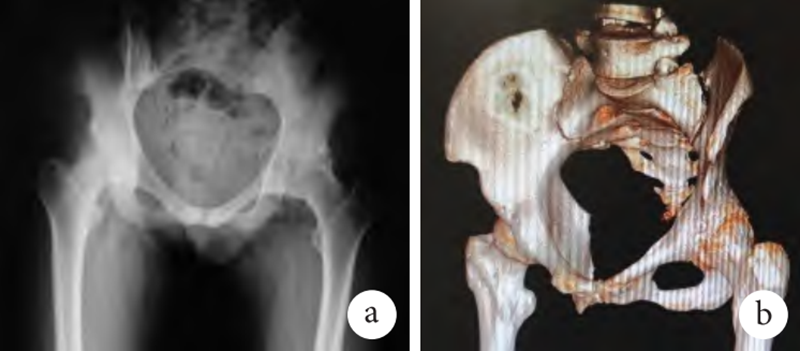

影像学检查:双髋关节正位 X 线片示左髋关节间隙消失,左侧股骨头形态异常,左髋关节僵硬(图 1a);髋关节+股骨 CT 平扫及三维重建示左侧髋关节僵硬,双侧骶髂关节炎(图 1b)。

图1 a.术前骨盆X线片;b.术前髋关节CT三维重建